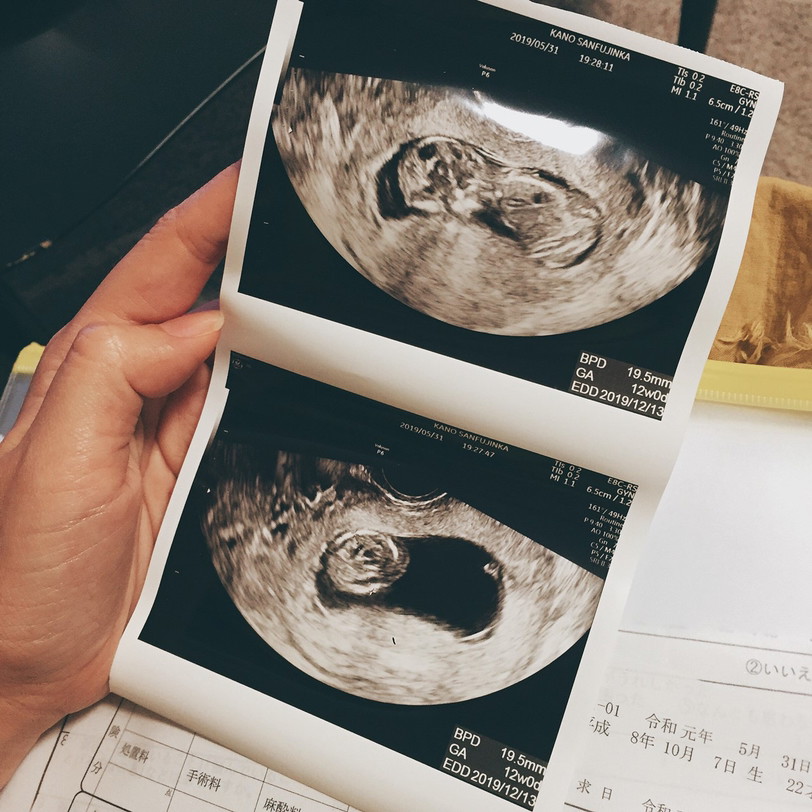

ตอน12วีคคะ ตอนนี้20วีคแล้ว